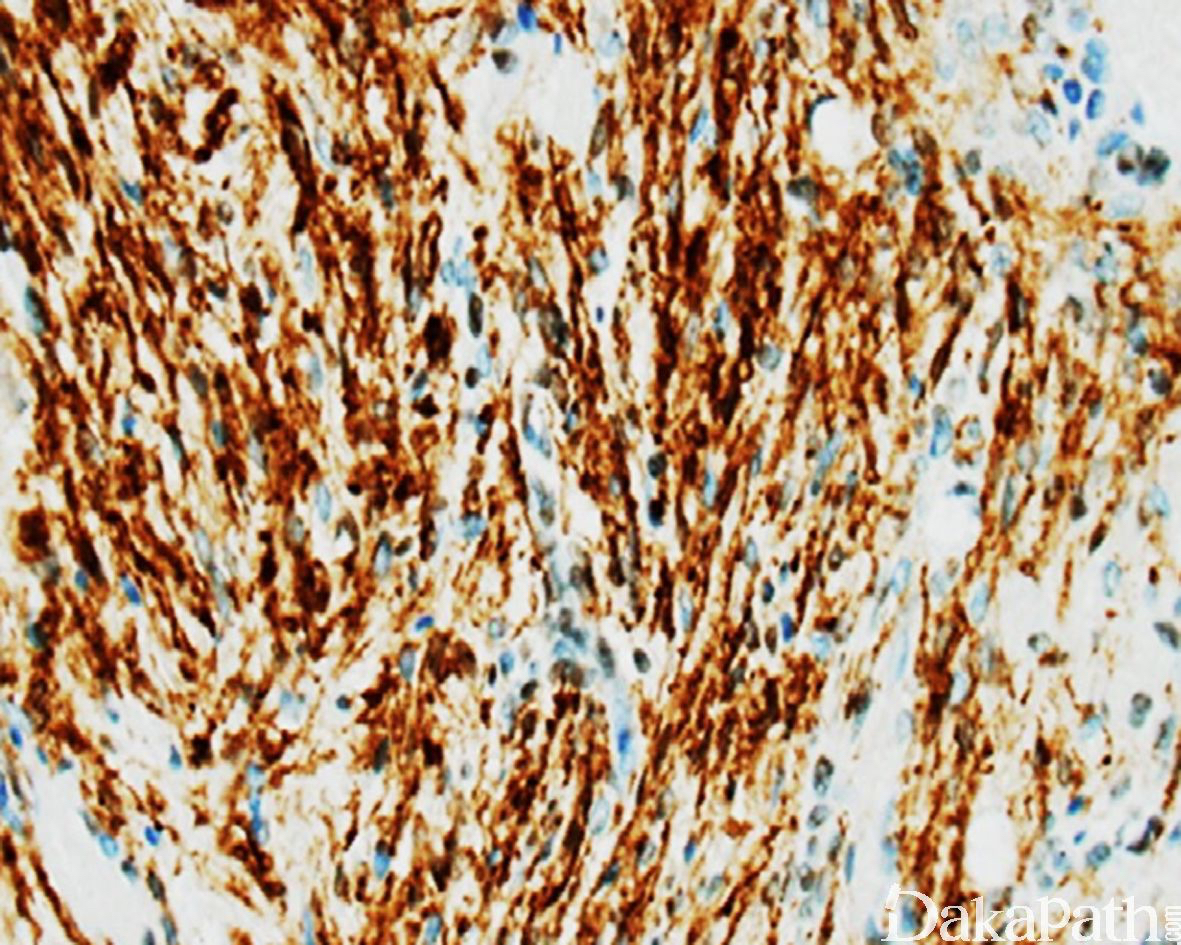

梭形细胞具有纤维母细胞性属性表达 vimentin 和 MSA,不表达 HHV8 和内皮细胞标志物;内皮细胞表达 CD31 和 CD34. ERG。网状纤维染色和勾勒出实行区域挤压的血管结构。